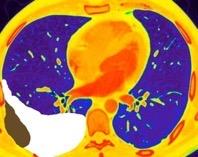

Tromboembolismo pulmonar.

Frecuencia del derrame:

Rx: 32%. TC: 47%

Unilateral. 85%

< 1/3 del hemitórax: 90%

Todos exudados

58% con eritrocitos

21% tabicación lo que causa demora en el diagnóstico

TEP. Empiema pleural. Atelectasia redonda

Porcel JM et al. Analysis of pleural effusions in acute pulmonary embolism: radiological and pleural fluid data from 230 patients. Respirology 2007/ Iguchi T et al. Desquamation of the subpleural lung parenchyma caused by empyema after pulmonary embolism: A case report. Respirol Case Rep. 2022 .